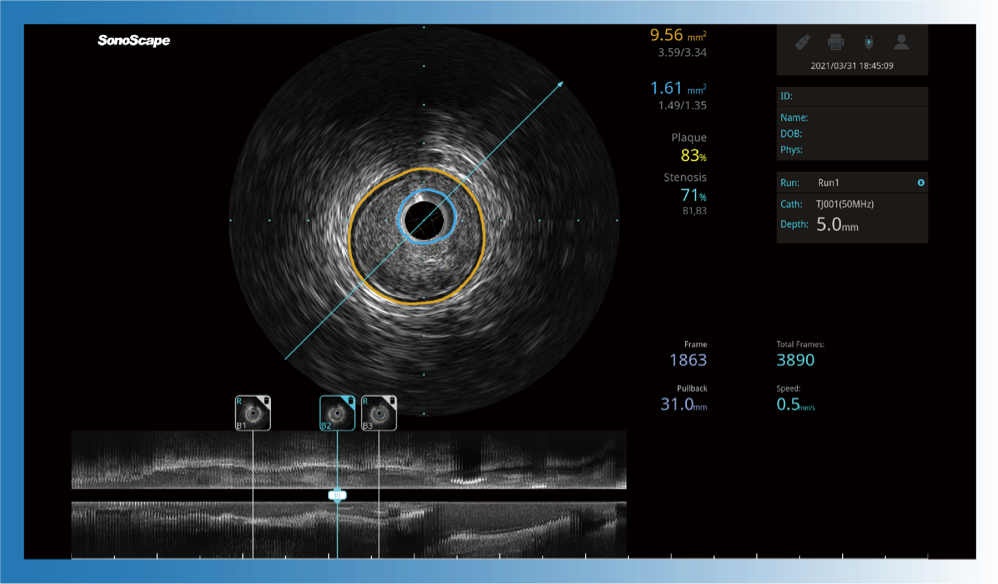

• 美狮贵宾会官网宽频IVUS图像

• 传统IVUS图像

对比传统IVUS导管成像,美狮贵宾会官网宽频IVUS图像的近场支架梁显影更细腻,远场中膜外血管仍清晰可辨,兼顾远中近,兼顾分辨力与穿透深度

一键智能描迹,自动测量斑块负荷、面积狭窄率等指标,准确率高于90%